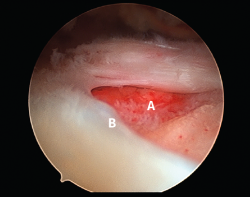

Figura 3. Rotura del manguito rotador en forma de L. A: tendón infraespinoso; B: tendón supraespinoso; C: glena; D: cabeza humeral.

Figura 5. Rotura de tipo C1. A: rotura pequeña de espesor completo del supraespinoso; B: cabeza humeral.

Sin embargo, las clasificaciones basadas en el tamaño de la rotura deben ser bidimensionales, ya que la visión unidimensional puede ser engañosa, al mostrar el tamaño de la rotura solo desde el plano anteroposterior(4). Por esta razón, proponemos el sistema de clasificación del manguito posterosuperior sugerida por Snyder, que aporta información no solo del tamaño, sino del número de tendones afectados y la presencia de tejido cicatricial(7). En las lesiones de tipo C1 la lesión atraviesa todo el espesor del tendón y en el eje transversal es pequeña y punzante (Figura 5). Las de tipo C2 son roturas de espesor completo pero la distancia entre los extremos de la rotura es menor de 2 cm con escasa retracción (Figura 6). En las de tipo C3 la rotura afecta en sentido transversal entre 3 y 4 cm con mayor retracción implicando 2 tendones (Figura 7). Y las de tipo C4 son la rotura masiva del manguito de los rotadores con una afectación de espesor completo de toda la anchura de 2 o más tendones asociando importante retracción (Figura 8).